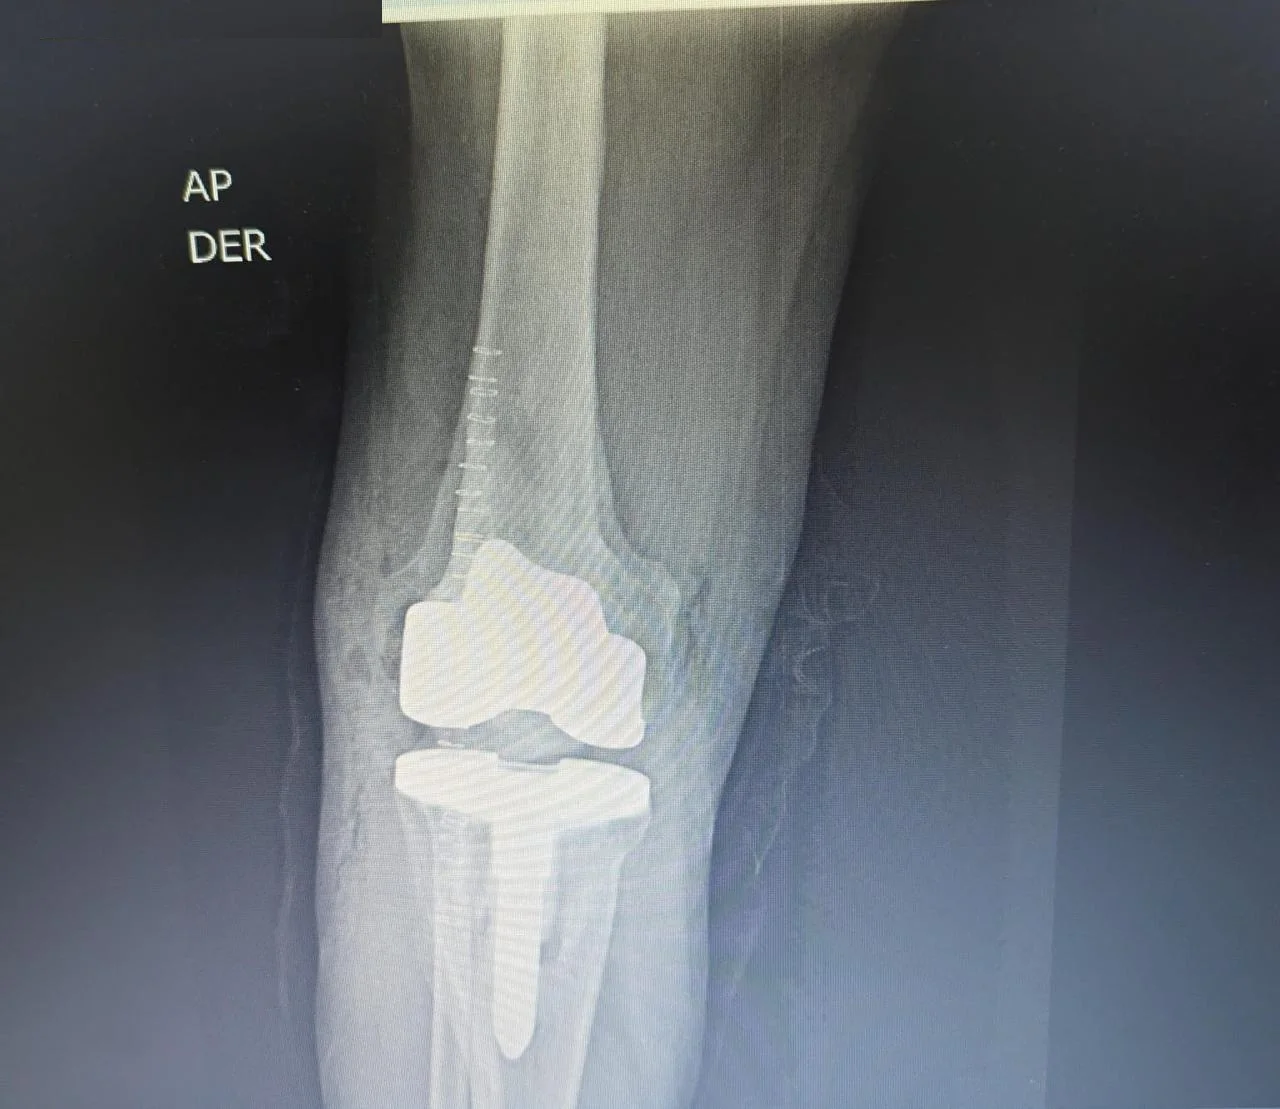

Antes Radiografía preoperatoria de fractura de tibia y osteoartrosis de rodilla

Después Radiografía postoperatoria de reemplazo articular de rodilla tras fractura de tibia

Traumatología

Reemplazo articular

Fractura de Tibia

• Perfil del Paciente: Masculino, 50 años.

• Historia Clínica: Antecedentes de 25 años de evolución con dolor crónico y pérdida de movilidad.

• Diagnóstico: Osteoartrosis secundaria a fractura de rodilla antigua.

• Resultado (Caso 2024): Intervención exitosa con recuperación completa. Actualmente el paciente presenta una evolución óptima y retorno a su vida cotidiana.